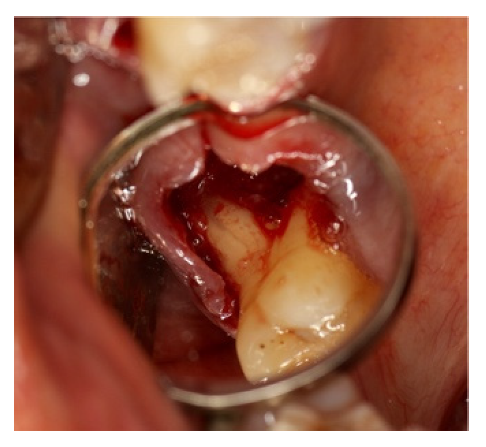

A large amount of infected granulation tissue was present in furcation space, between the distal-buccal and palatal root (Figure 20).

Figure 20.

Furcation lesion between the distal buccal root and the palatal tooth 1.6 after 1.7 extraction.

The alveolar cavity and roots were curetted and cleaned with a solution of physiological water and hydrogen peroxide 1:1 and collagen sponges, completely wetted by the blood from the surgical site, were applied and followed by the protective positioning of a shaped foil.

After three months, the foil was removed (Figure 21a,b) and the roots surface previously exposed, appeared covered by bone.

Figure 21.

(a) Removal of sutures after 3 weeks; (b) extensive healing tissue is observed which has completely covered the previously exposed roots.